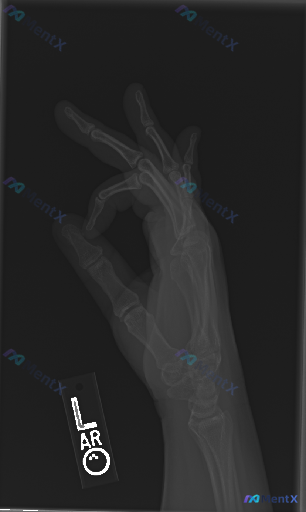

整理到一张左手X光的影像资料,大家可以一起讨论下解读思路: - 影像标记为“L”,是左手的投照 - 但不是标准的正位/侧位/斜位,而是手部处于“OK”手势(拇指与食指捏合)的特殊体位 - 图像清晰度尚可,能看到基本骨性结构 - 当前投照下,各掌骨、指骨骨皮质连续,未见明显骨折线或脱位;关节间隙也没有...